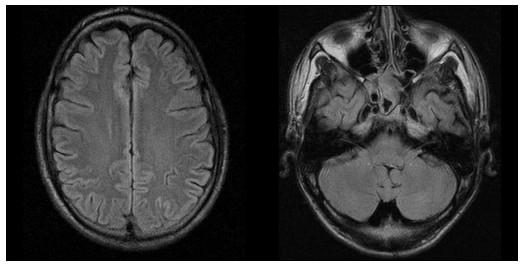

A 21-year-old Caucasian man with Goodpasture's disease and end-stage renal disease presented with two generalized seizures after a period of mild cognitive disturbance. Blood pressure and routine laboratory tests did not exceed the patient's usual values, and examination of cerebrospinal fluid was unremarkable. Cerebral magnetic resonance imaging (MRI) revealed multiple cortical and subcortical lesions on fluid-attenuated inversion recovery sequences. Since antiglomerular basement membrane antibodies were found to be positive with high titers, plasmapheresis was started. In addition, cyclophosphamide pulse therapy was given on day 13. Encephalopathy and MRI lesions disappeared during this therapy, and antiglomerular basement membrane antibodies were significantly reduced. Previous immunosuppressive therapy was performed without corticosteroids and terminated early after 3 months. The differential diagnostic considerations were cerebral vasculitis and posterior reversible encephalopathy syndrome. Vasculitis could be seen as an extrarenal manifestation of the underlying disease. Posterior reversible encephalopathy syndrome, on the other hand, can be triggered by immunosuppressive therapy and may appear without a hypertensive crisis.

一名21岁患有古德帕斯丘病和终末期肾病的白种男性,在经历一段轻度认知障碍后出现两次全身性癫痫发作。血压和常规实验室检查未超过患者的通常值,脑脊液检查无异常。脑部磁共振成像(MRI)在液体衰减反转恢复序列上显示多个皮质和皮质下病变。由于发现抗肾小球基底膜抗体高滴度阳性,遂开始进行血浆置换。此外,在第13天给予环磷酰胺脉冲治疗。在此治疗期间,脑病和MRI病变消失,抗肾小球基底膜抗体显著降低。先前的免疫抑制治疗未使用皮质类固醇,3个月后提前终止。鉴别诊断考虑为脑血管炎和后部可逆性脑病综合征。血管炎可视为潜在疾病的肾外表现。另一方面,后部可逆性脑病综合征可由免疫抑制治疗引发,且可能在无高血压危象的情况下出现。